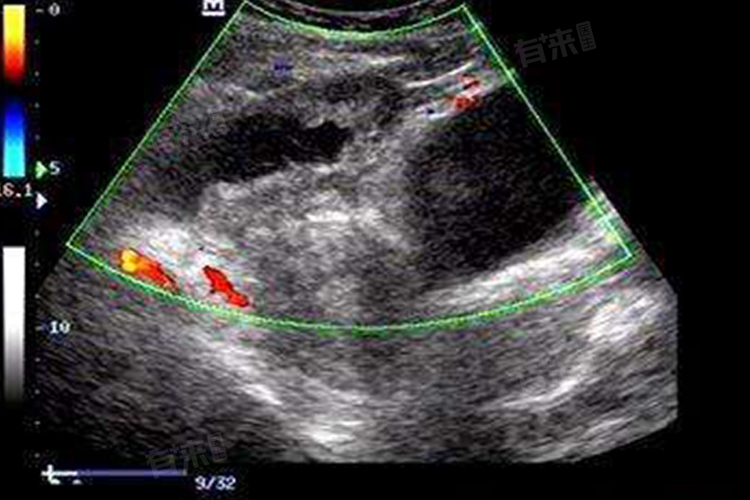

- 肿瘤:良性肿瘤如卵巢浆液性囊腺瘤,肿瘤细胞分泌大量液体,积聚在瘤体内,超声下呈现边界清晰的囊性回声,手术切除多可治愈。恶性肿瘤如卵巢癌,生长过程中因肿瘤内部缺血坏死、液化,形成囊性区域,这种囊性回声通常形态不规则,囊壁不光整,还伴有丰富血流信号。